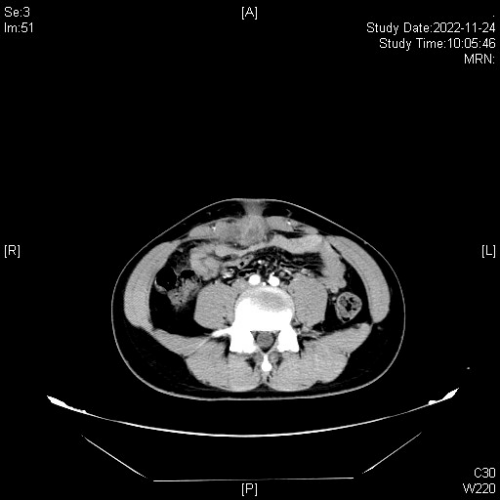

入院后,进一步完善腹部CT检查,显示脐部软组织肿胀,脐部后下方边缘强化囊性灶,大小约27mm*24mm*35mm,其周脂肪间隙模糊,脐部向膀胱方向可见一瘘管,向膀胱方向延伸,符合脐尿管瘘并感染的诊断。雷志盛考虑患者脐尿管瘘并严重感染,决定尽快实施腹腔镜下微创手术。完善术前准备后,术中先在病人在腹部打了3个大小约0.5-1.0cm的小孔,然后通过腹腔镜将脐部下方的病灶剥离,剥离至膀胱尖部,发现瘘管与膀胱相通,下端用切割缝合器关闭脐尿管瘘和膀胱之间的通道,将瘘管完整剥离。剥离下的瘘管剪开后可见大量脓液和坏死组织,还可见到粪石,瘘管下端有一清晰管道结构通向膀胱。手术顺利,且创伤小,术后李星恢复良好。